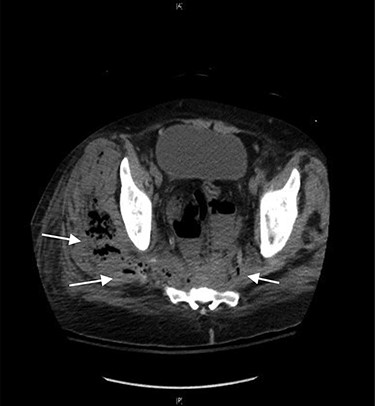

Marked improvement was seen on CT post-operative day 5 (Fig. 3). MRI of the pelvis showed marrow edema in the sacrum and coccyx, which was consistent with osteomyelitis and complex fluid collections of the right pelvis and right upper thigh, which was likely tracking from the presacral process. A CT guided drain placement was done for the right thigh abscess. Repeat MRI on day 14 showed resolution of the pelvic abscess, sacral osteomyelitis and myositis of the left gluteal and iliacus muscles. The patient was taken back to the OR to remove the rectal drain and replace it with a transperineal drain. This was carried out to allow the rectal perforation to heal and to provide continued drainage given the persistent myositis and osteomyelitis. The patient was started on steroids for his Crohn’s disease with plans to switch to biologic therapy. The transperineal drain was removed on post-operative day 25, and he was discharged home on biologic therapy with tapering of his steroid regimen.

Computed tomography (sagittal and axial views) showing post-operative resolution of the presacral abscess (post-operative day 5).